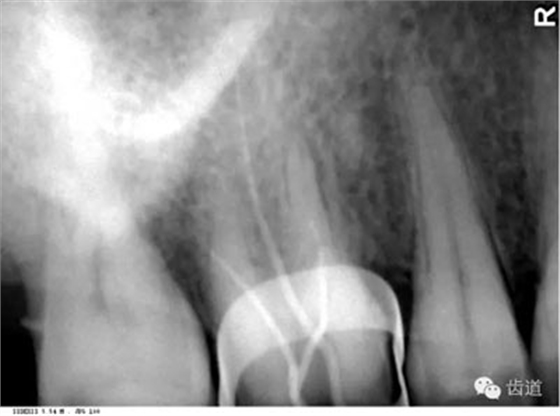

4)外斜線:

由升支前緣下部斜向前下方,為一密度高的帶狀影像。常重疊在第二、三磨牙牙冠處、頸部或根部,使牙髓室或根管不能清晰顯示